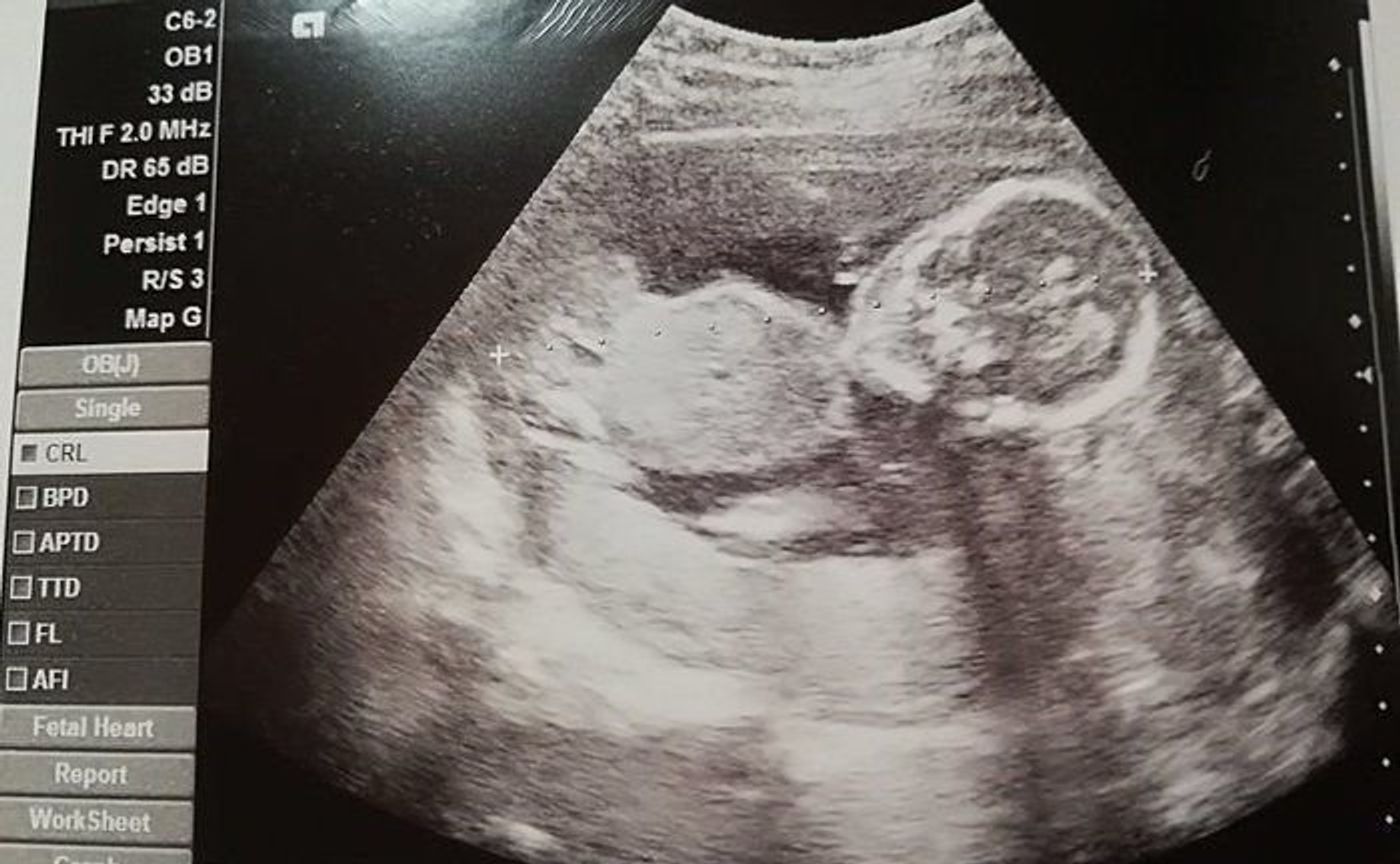

6分 助産師 安定期に入ると外に出かけたくなるママも多くなりますよね。 外に出ることは気分転換にもなるのでおすすめです。 しかし以下の注意事項に気 妊娠18週目になりました。 この時期は つわりが終わることで食欲がでてきたりするようです。 一方子宮が大きくなってくる分、 胃が圧迫され息切れがしやすくなる とも言われているので無理していけません。 今回は検診に行ってきたので、エコー写真があります。

妊娠19週目妊娠線の予防・ケアの時期?胎動が分からない場合も? 妊娠16週目安定期に突入もつわりはぶり返し胎動も感じない日々 妊娠17週目エコーで性別が確定する時期!胎動はどんな感じ? 妊娠22週目胎動が急に感じなくなった?妊娠18週エコー検査 妊娠14週です。 次回18週の健診で自費のエコーが30分あります。希望したわけではなく、病院側で、決まっているものでした。 医師からは、ほとんど説明がありませんでしたが、 通常とどのようなことが異なるのでしょうか? 18週0日でのエコーです。 性別はまだわからないと言われたのですが、わずかな突起?が男の子のような気がして。 上が女の子なのでいまいちわかりません。 お股自体はしっかり見えてるのに18 週でわからないとなると、また女の子?と思ってしまって。